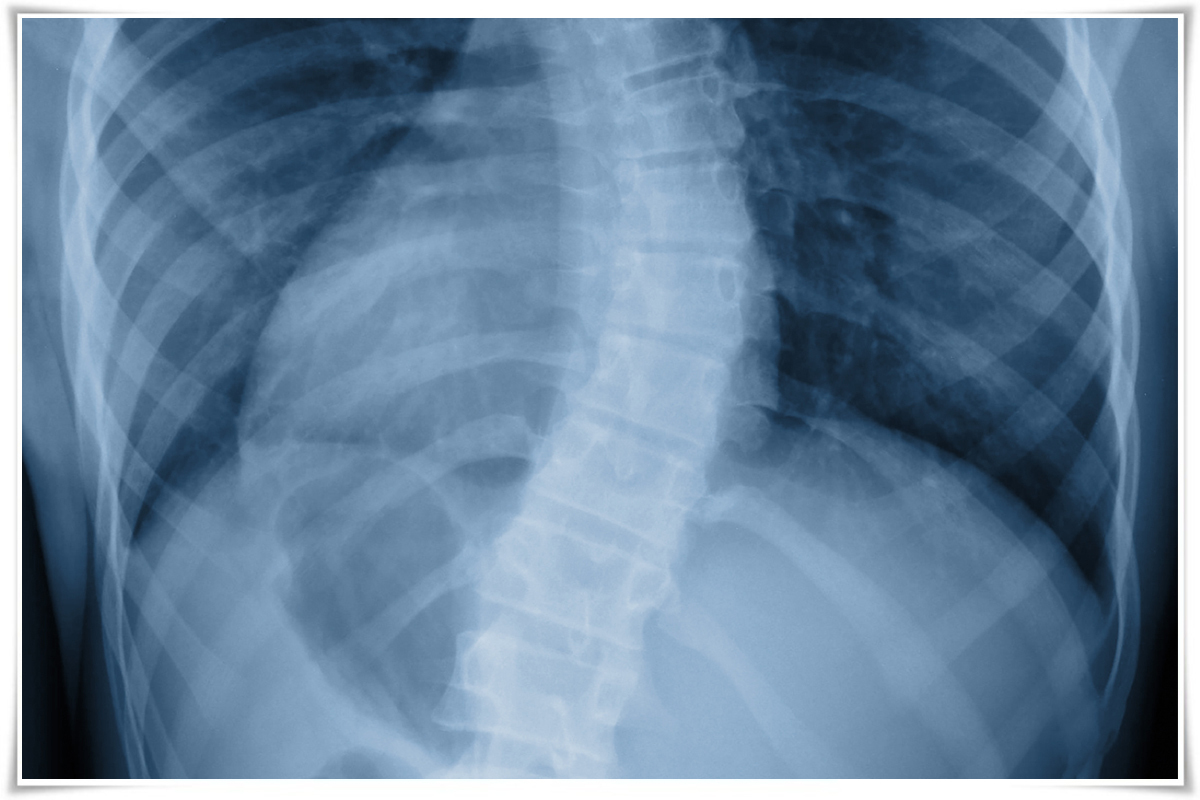

▶척추측만증◀

정면으로 봤을 때 일자 모양으로 있어야 할 척추가 C자 또는 S자 형태로 휘거나 옆으로 굽는 경우를 말합니다.